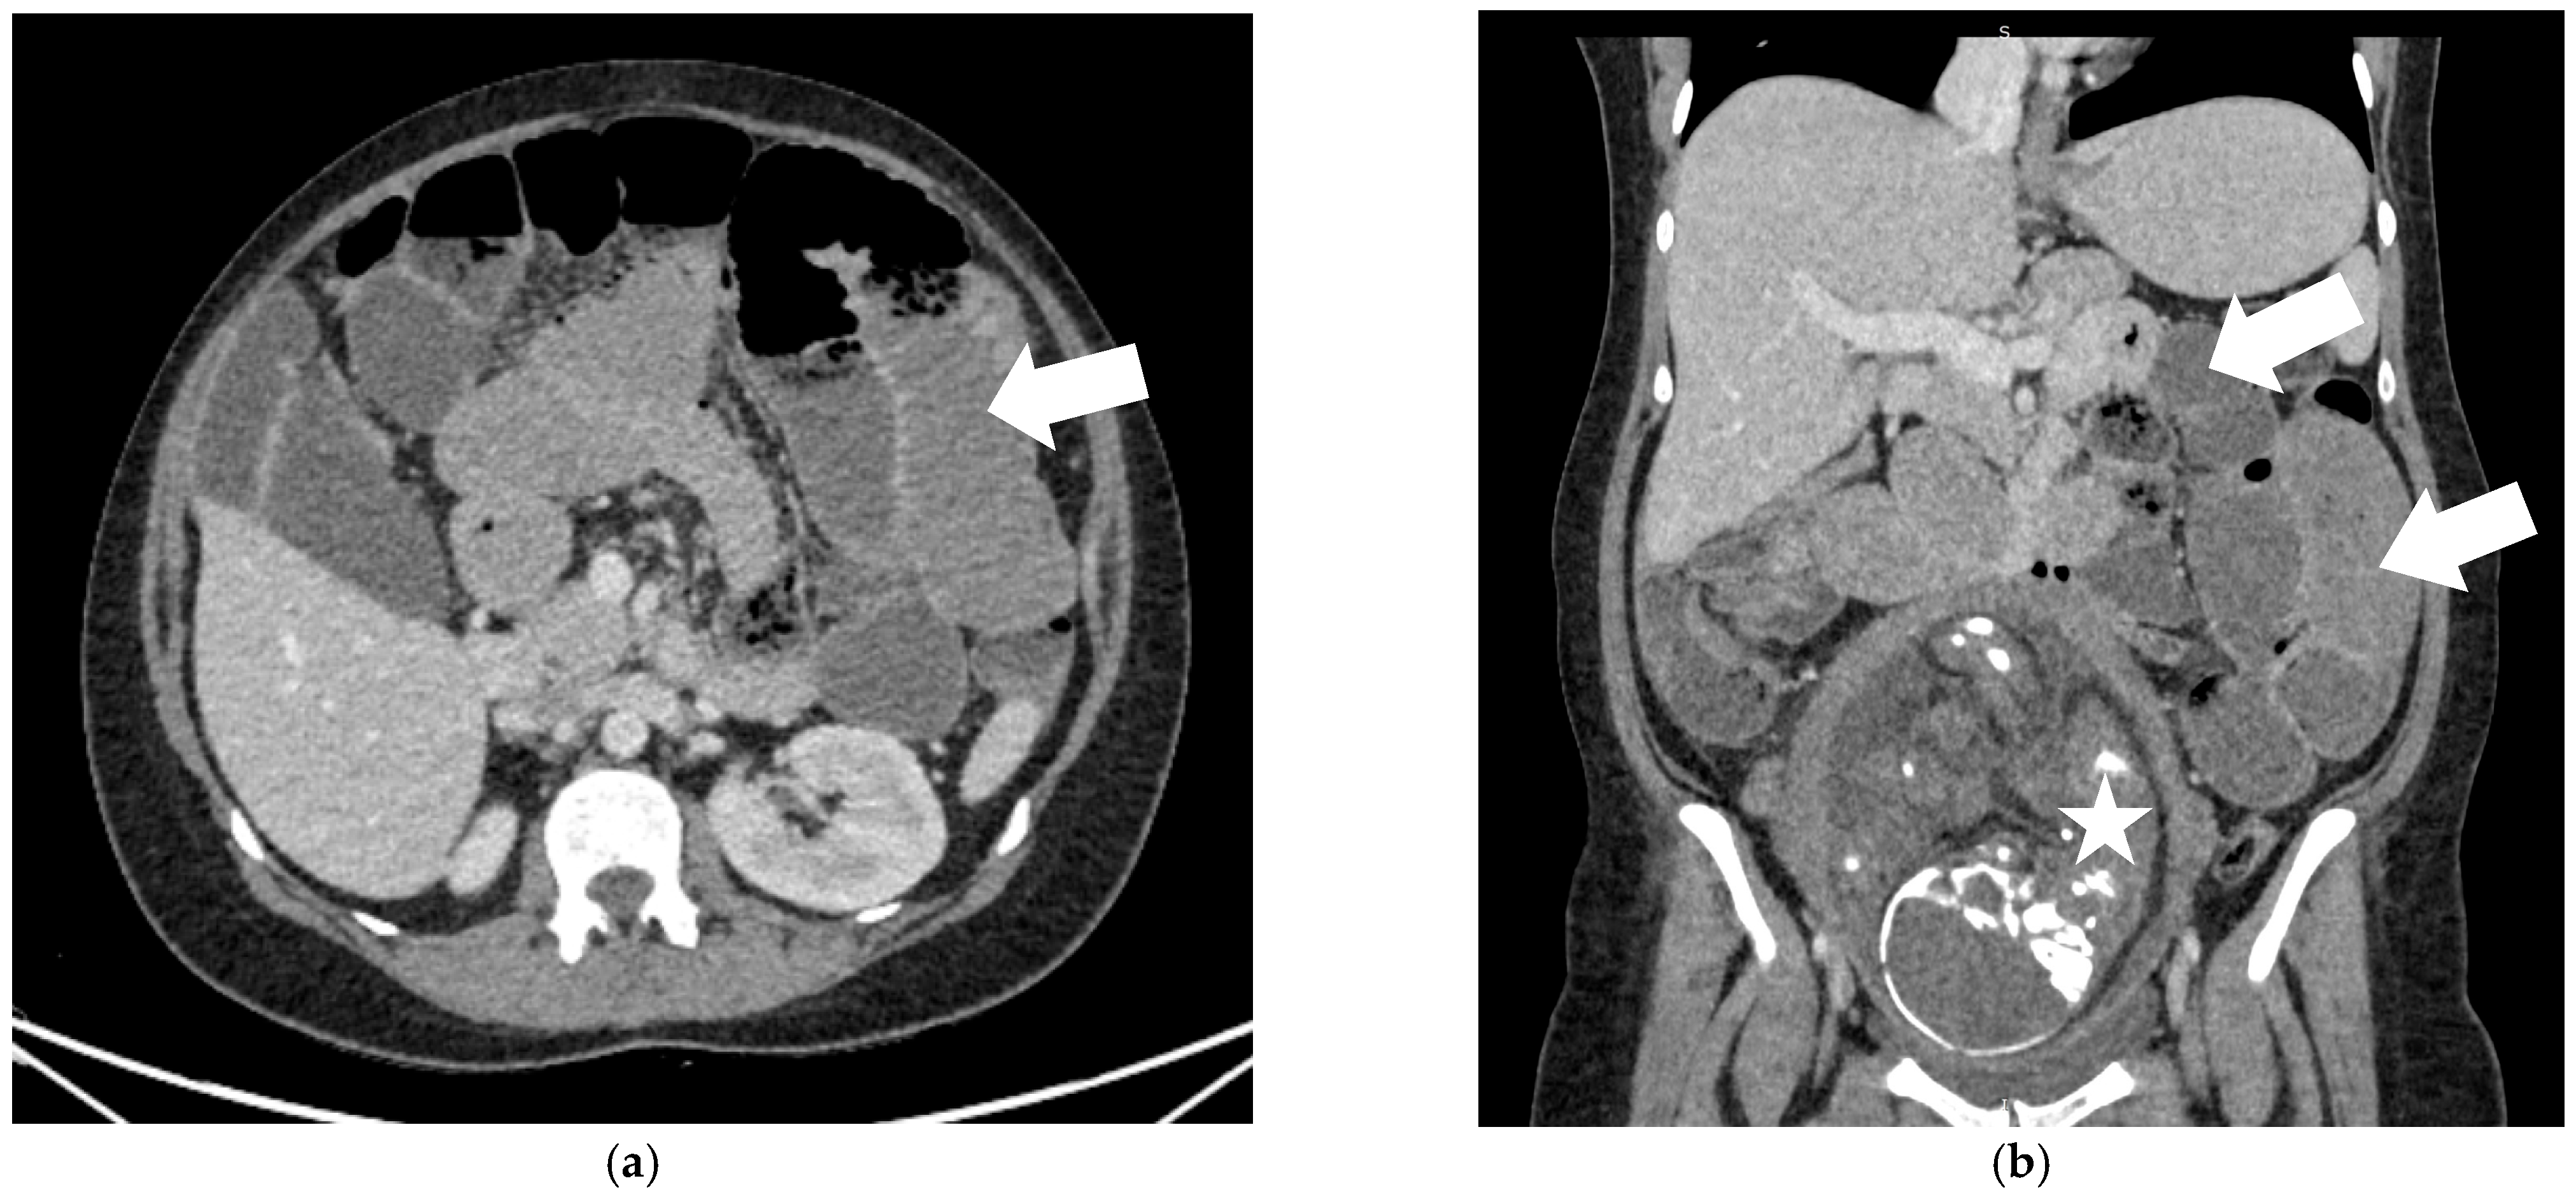

2. Case Report